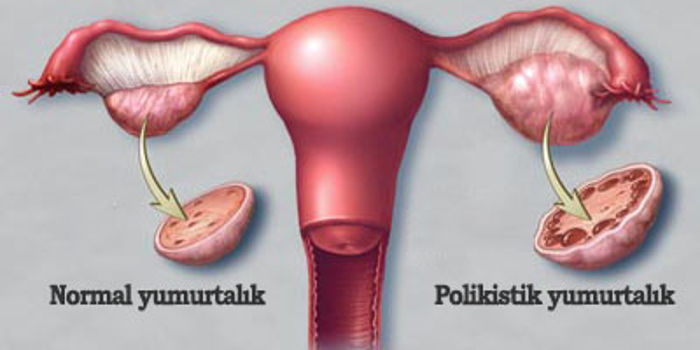

— Yumurtlama bozuklukları ; polikistik over sendromlu hastaların

yumurtalıklarında çok sayıda içi sıvı dolu kesecik (folikül) vardır ve bu kesecikler ,olgunlaşıp

yumurtlama aşamasına gelemezler ve dolayısıyla “yumurtlama olmaz”.

— Yumurtalıklarda kist oluşumu ; polikistik over sendromlu hastaların

yumurtalıkları çok sayıda içi sıvı dolu kesecikle doludur.Buna bağlı olarak ta

yumurtalıklar,normalin 2-3 katına kadar büyürler.

Polikistik over sendromu teşhisi koyabilmek için,hastadan alınan anamnez ve

muayene bulguları önemlidir.Günümüzde ultrasonografi,özellikle transvajinal

ultrasonografi,tanıda oldukça önemli bir yere sahiptir.Ultrasonografide yukarıda belirttiğimiz

çok sayıdaki küçük kistler ,çok net bir şekilde gözlenir.Bu kistler,gelişmeye başlayan ancak

yumurtlamaya kadar gidemiyen foliküllerdir.Polikistik over ,içerisinde kistler barındıran

yumurtalıkların ultrasonografideki görüntüsüdür,halbuki polikistik over sendromu ise,bu